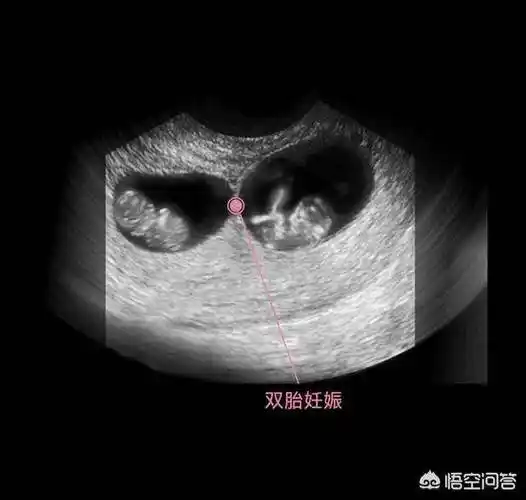

一个孕囊两个胎芽图片

是否可以诊断早期双胎? [病例帖]

如一个孕囊内有两个卵黄囊及两个胚芽,则为单卵双胎附:早期妊娠天数及

50天早孕双胎妊娠(双孕囊)